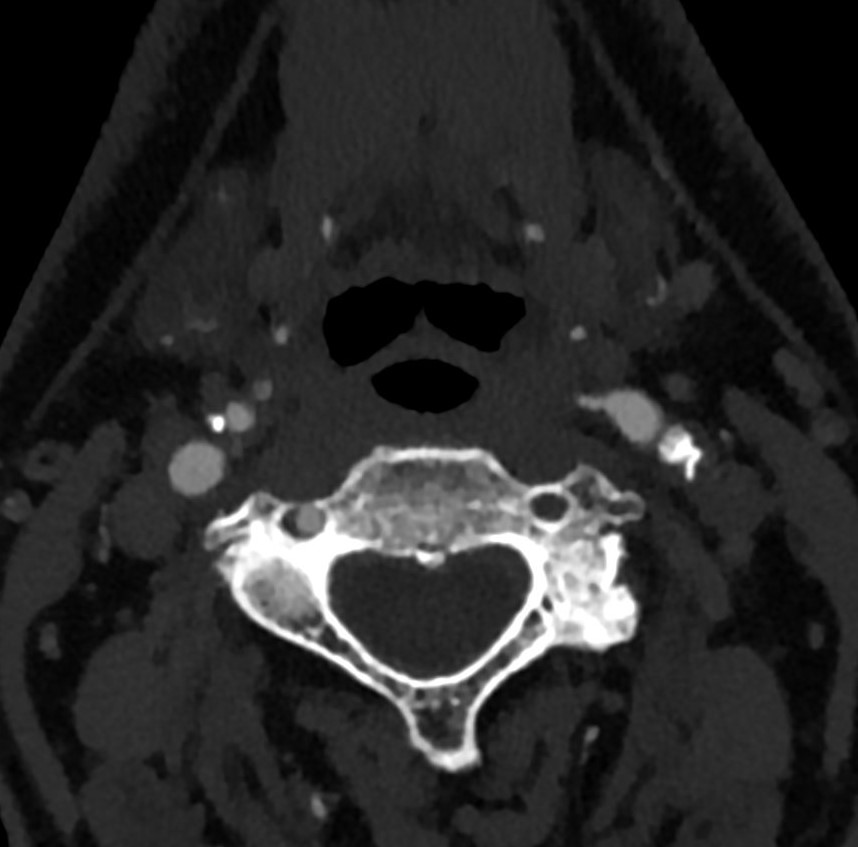

Image

Contrast enhanced MR angiography

CT angiography – volume rendering

Fig. 11., 12.: Coarctatio aortae